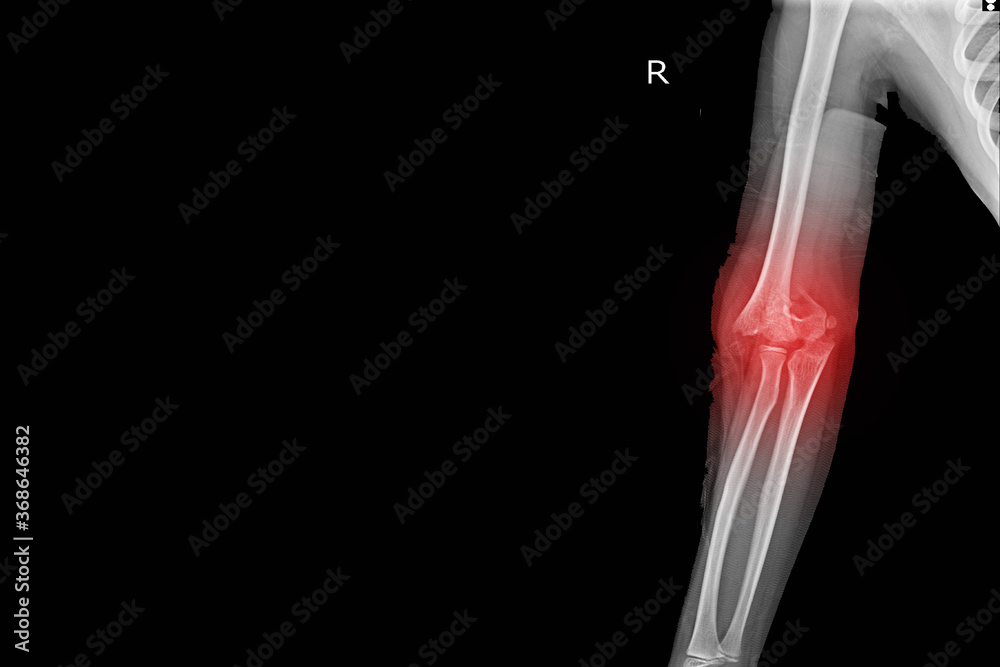

Xray Elbow joint Finding Supracondylar fracture distal humerus with X Ray Elbow Joint Effusion this review article discusses the evidence linking elbow effusion with occult fractures. The sail sign is the key to recognizing an elbow joint effusion. an elbow joint effusion is a key finding to recognize on an elbow radiograph. Possible causes include a fracture or other damage due to trauma, overuse injury, a sprain, infection, or arthritis. joint. X Ray Elbow Joint Effusion.

Xray Elbow Joint Finding Supracondylar Fracture Distal Humerus with X Ray Elbow Joint Effusion using deep learning it is possible to achieve expert level diagnostic accuracy in elbow joint effusion. Possible causes include a fracture or other damage due to trauma, overuse injury, a sprain, infection, or arthritis. this review article discusses the evidence linking elbow effusion with occult fractures. an elbow joint effusion is a key finding to recognize on. X Ray Elbow Joint Effusion.